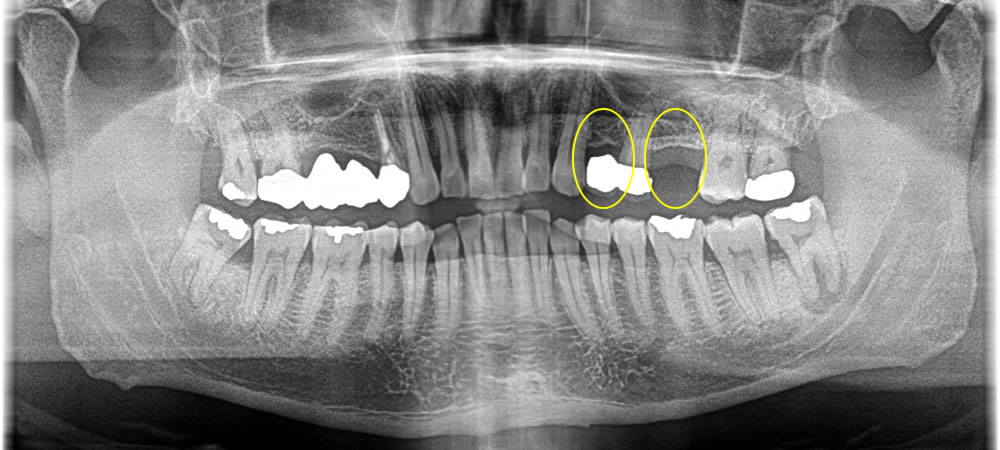

歯の欠損部をインプラントで治療した症例

こちらの患者さまは、元々歯が無くなってしまっている部位にインプラント治療を行いたいとのご希望で来院されました。

手前の歯は審美的に気になるという事でした。当該部分は骨がしっかりとあり、即時荷重が可能な状態なためインプラント埋入と同時に仮の歯を装着しました。また、手前の歯は6ミリ程度の切開で行ったため、縫合もなく痛み腫れもほぼ無く施術できました。